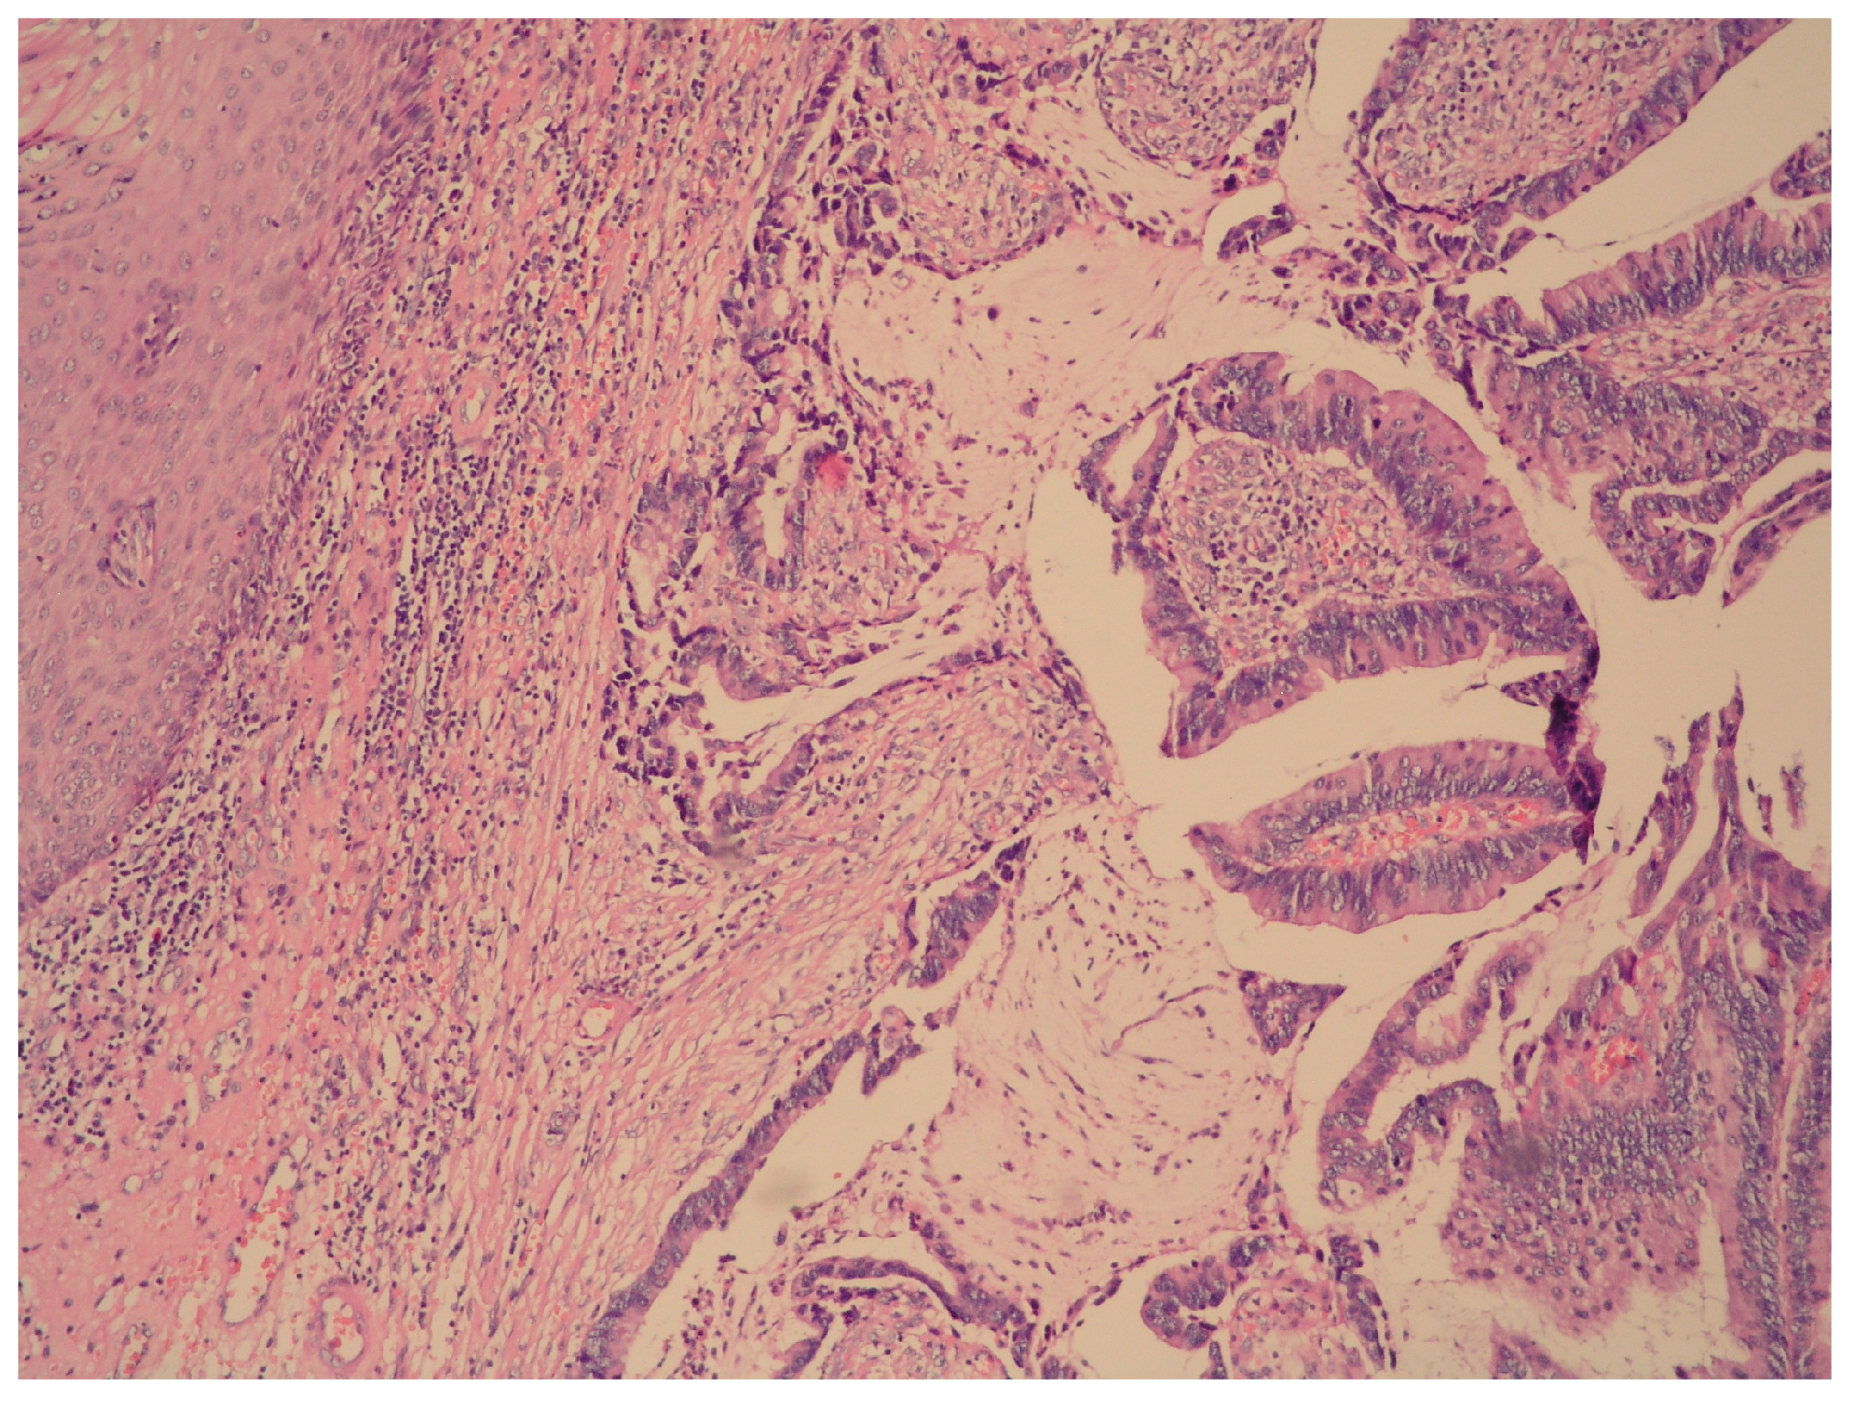

Primary Vaginal Mucinous Adenocarcinoma of Intestinal Type—Clinical, Radiological and Morphological Aspects

2. Case Presentation